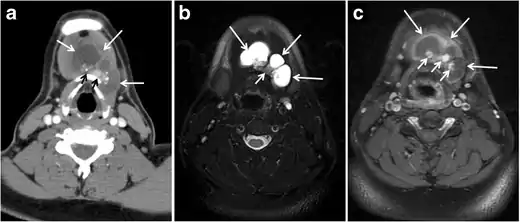

Fig. 6. A 61-year-old female patient with locally aggressive PTC. an Enhanced axial CT scan of the neck demonstrates a heterogeneous infiltrative thyroid mass. This mass diffusely involves the entire gland and circumferentially encases the trachea with involvement of bilateral tracheoesophageal grooves (white arrows). b, c Additional axial cranial images show right cricoid cartilage destruction (black arrows in b), right thyroid cartilage destruction (black arrow in c), right vocal cord paralysis (white arrows in b), and bilateral cervical lymphadenopathy (arrowheads).[1]

Thyroid lymphoma represents about 5% of thyroid malignancies. Non-Hodgkin's lymphoma is the most common type and can be secondary to generalized lymphoma or a primary tumour. Primary thyroid lymphoma usually pre-exists with Hashimoto's thyroiditis. On CT scans with and without contrast, lymphomas tend to have low attenuation values. Thyroid lymphomas have variable appearance and mostly manifest as a solitary mass (80%). They may also manifest as multiple nodules (15% to 20%) or as a bulky mass replacing the entire gland with extra-thyroid extension (Figs. 11 and and12).12). The presence of cervical lymphadenopathy supports such a diagnosis. Although it is uncommon, tumour necrosis has been reported.[1]

Fig. 11. Thyroid non-Hodgkin's large B-cell lymphoma in a 66-year-old female patient. an Axial enhanced neck CT scan demonstrates left thyroid lobe and isthmus homogeneously hypodense and minimally enhancing mass (white arrows). This lesion invades the prevertebral muscles (black arrows). Note the multiple enlarged level V lymph nodes (white arrowheads). b Post-treatment image shows significant reduction in size and mass effect of the left thyroid infiltrative mass, with almost complete resolution of the left cervical lymphadenopathy.[1]

Fig. 12. Diffuse thyroid large B-cell lymphoma in 79-year-old female patient. an Axial enhanced neck CT scan demonstrates a homogeneously hypodense and minimally enhancing large right thyroid solid mass (long white arrow) extending into the thyroid isthmus. It is encasing the right carotid artery (short white arrow) and displacing of the trachea and oesophagus to the left side.[1]